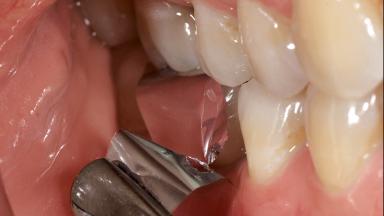

In this case, Nicola Zitzmann describes the sudden loss of a previously well-osseointegrated implant that had been in healthy function for 5 years. The case includes recommendations for occlusion and function of implant restorations. A 74-year-old patient had received implant-fixed dental prostheses in the maxilla in 2008, and in the right mandible three years later. His tooth loss was mainly related to recurrent caries associated with hyposalivation as a potential side effect of his cholesterol-lowering medication.